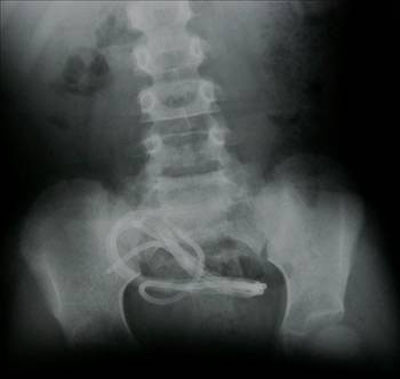

Galerinin tamamı için tıklayınızMideye kaçan sineği öldürmek için ağza sheltox sıkmak suretiyle ölüm (İstanbul/Sultanbeyli)

Mideye kaçan sineği öldürmek için ağza sheltox sıkmak suretiyle ölüm (İstanbul/Sultanbeyli)